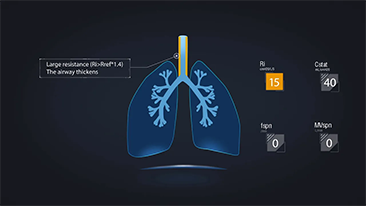

Door het diepgaande inzicht in de klinische behoeften van zowel pati?nten als zorgverleners, ondersteunen Mindray-beademingsapparaten de vereiste sequenti?le therapie bij zuurstoftherapie, niet-invasieve beademing en invasieve beademing met stabiele prestaties, veelzijdige functionaliteit en gebruiksgemak. Beademingsmodi en besluitvormingstools zijn ontwikkeld op basis van klinische behoeften en professionele richtlijnen, zodat medisch personeel rustig klinische beslissingen kan nemen voor alle pati?ntenpopulaties en alle ernstniveaus.

Het kiezen van de juiste beademingsinstellingen voor de behandeling van pati?nten met aandoeningen van de luchtwegen is een vrij belangrijke kwestie. Aangezien de taak van het specificeren van de parameters van beademingsapparatuur volledig wordt uitgevoerd door een arts, heeft de kennis en ervaring van de arts bij de selectie van deze instellingen een direct effect op de nauwkeurigheid van zijn/haar beslissingen. Het paradigma van de ondersteunende zorg voor pati?nten is in de afgelopen 20 jaar sterk veranderd. Tegenwoordig zijn er verschillende beademingsmodi en beslissingsondersteunende hulpmiddelen ontwikkeld rond klinische behoeften om zorgverleners te helpen effici?nter te werken en fouten bij klinische beslissingen te voorkomen.

De beademingsapparaten van de 3-in-1 SV Series integreren zuurstoftherapie met hoge flow, non-invasieve beademing en invasieve beademing voor stabiele prestaties, veelzijdige functionaliteit en gebruiksgemak. Uitzonderlijke longbeschermende eigenschappen en veel tools voor besluitvorming ontworpen om het risico op kruisbesmetting te verminderen en de dagelijkse last van zorgverleners te verlichten.